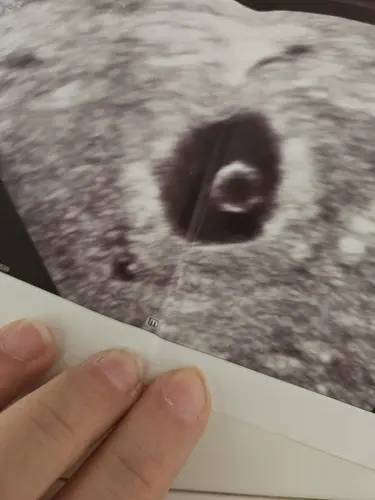

Was is das runde das is bei mir auch so?🙈

Der dottersack und es sieht ähnlich aus

Das ist der dottersack

🥺🥺 Hab so angst da kein Kind kommt... aber eig is ein dottersack ja ein gutes Zeichen

Ja definitiv

Also ja eig ein gutes Zeichen 🥺